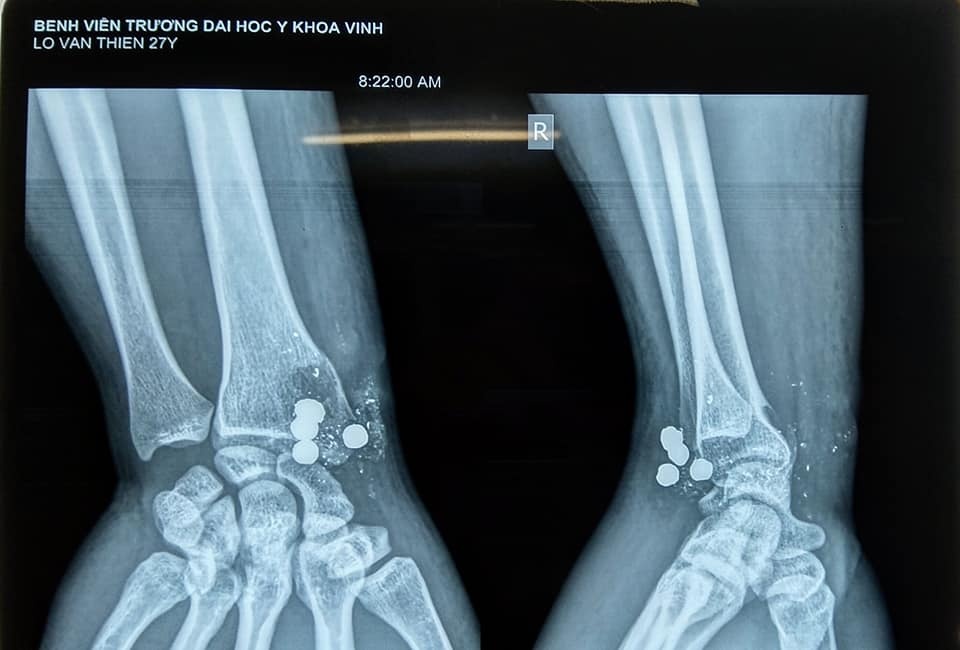

Hình ảnh xương quay vỡ và các mảnh đạn ở cổ tay bệnh nhân. Ảnh: BVCC.

Qua kết quả khám và chụp chiếu tại bệnh viện, bác sĩ phát hiện anh T. bị vỡ đầu dưới xương quay, tổn thương cung động mạch gan tay sâu, không tổn thương gân gấp duỗi và các dây thần kinh. Trong cổ tay anh T. còn 4 mảnh bạn lớn bằng chì và nhiều mảnh kim loại nhỏ khác. Một viên lớn đã xuyên từ trước ra sau.